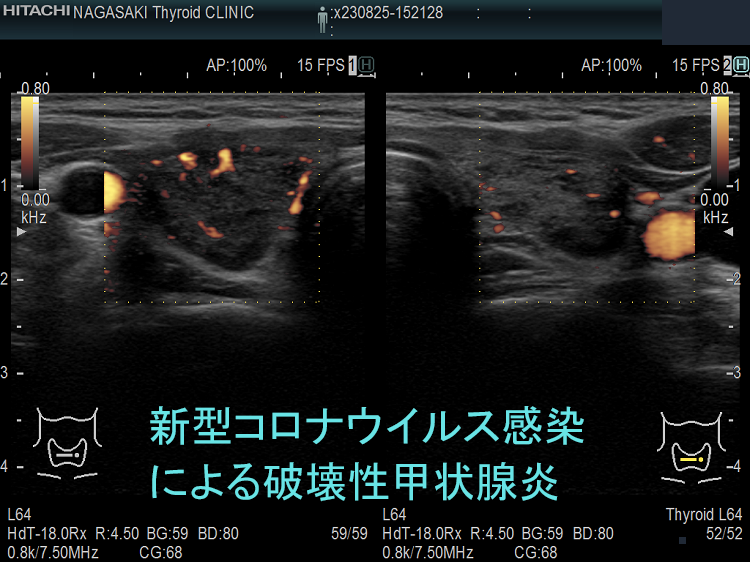

下の写真は、新型コロナウイルス肺炎に罹った甲状腺機能正常橋本病患者の感染前後計12か月の超音波(エコー)画像です。新型コロナウイルス肺炎になる6か月前と6カ月後に、1年に1回の定期検査で長崎甲状腺クリニック(大阪)を訪れていました。新型コロナウイルス肺炎発症時の甲状腺機能は不明ですが、少なくとも6カ月後は正常でした。しかし、発症前に比べて甲状腺は腫大し、腹側(写真下部)の低エコー領域(黒い部分)が拡大しており、橋本病の炎症が増悪したと推察されます。新型コロナウイルス肺炎発症時には破壊性甲状腺炎(無痛性甲状腺炎)を起こしていても不思議ではありません。

以下は、長崎甲状腺クリニック(大阪)の自験例です。

長崎甲状腺クリニック(大阪)の自験例

急性期

1.5か月後

5か月後